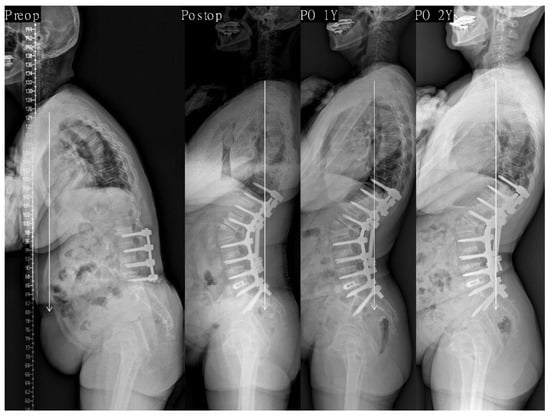

| Variables | Last Balanced Group (n = 195) | Last Non-Balanced Group (n = 33) | p-Value |

|---|---|---|---|

| SVA (mm) | |||

| Preoperative | 200 ± 65 | 193 ± 79 | 0.609 |

| Postoperative | −14 ± 26 | 0 ± 34 | 0.062 |

| Last f/u | −2 ± 27 | 70 ± 24 | <0.001 * |

| Lumbar lordosis (°) ‡ | |||

| Preoperative | 1 ± 20 | 0 ± 17 | 0.208 |

| Postoperative | −69 ± 10 | −61 ± 14 | <0.001 * |

| Last f/u | −64 ± 11 | −58 ± 18 | 0.028 * |

| PI-LL (°) | |||

| Preoperative | 57 ± 20 | 55 ± 16 | 0.643 |

| Postoperative | −13 ± 11 | −4 ± 14 | <0.001 * |

| Last f/u | −9 ± 10 | 0 ± 14 | 0.001 * |

| Pelvic tilt (°) | |||

| Preoperative | 30 ± 13 | 30 ± 16 | 0.907 |

| Postoperative | 9 ± 10 | 13 ± 9 | <0.001 * |

| Last f/u | 13 ± 10 | 22 ± 8 | <0.001 * |